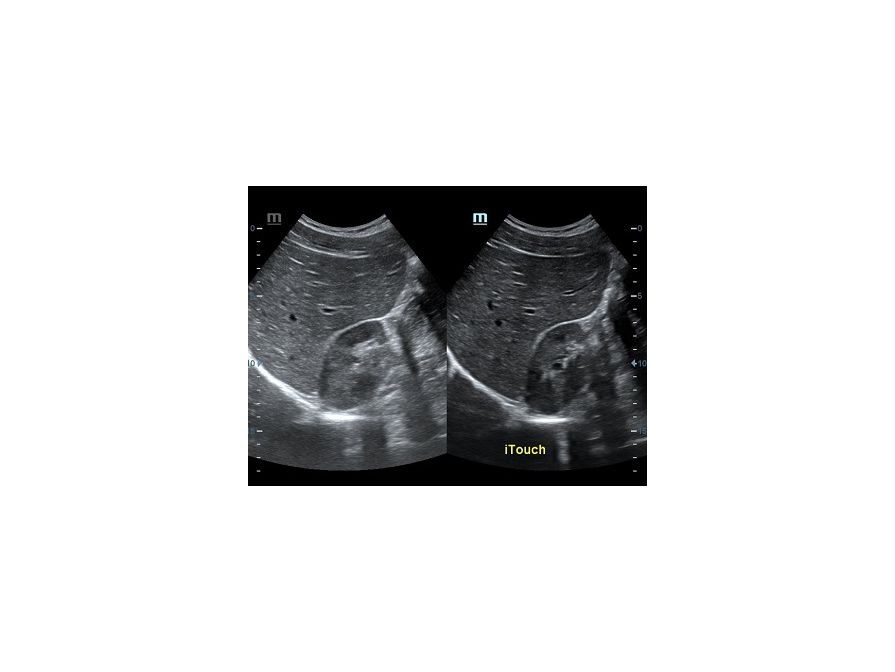

Оптимизация изображения происходит и за счет постобработки. Наиболее часто используемый инструмент - общее усиление (Gain). Усиление делает изображение «ярче», но чем сильнее усиление, тем меньше различия между структурами. Также используются усиление по времени (TGC) и усиление по длине (LGC), которые позволяют изменять отображение на экране послойно, позволяя подсветить гипоэхогенные участки, или, наоборот, снизить визуально эхогенность слишком ярких моментов. Данный вид оптимизации требует много времени, для упрощения работы доктора на приборах Mindray внедрена система автоматической оптимизации - iTouch.